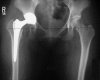

Background: Offset in THA correlates to abductor muscle function, wear, and impingement. Femoral offset after THA is not independent of the cup center of rotation (COR) so hip offset, a combination of femoral offset and change in hip COR, becomes the important measurement.

Methods: We compared hip offset of arthritic and contralateral normal hips on radiographs in 82 patients (82 hips) who had THA. We used computer navigation in all patients with the aim of reconstructing the hip offset and to compare hip offset change to the quantitative change of the hip COR.

Results: The preoperative radiographic change to equalize the offset ranged from -12 to +21 mm (mean, 1.5); postoperatively the change was 1.4 ± 6.4 mm and was within ± 6 mm in 78 of 82 hips. As COR displaced superiorly from 3 to 6+ mm the offset had to be substantially increased. Only with COR 0-3 mm superior and 0-5 mm medial was offset always within 5 mm.

Conclusions: Hip offset reconstruction was directly related to the position of the hip COR, and navigation allowed quantitative control of offset and hip length.